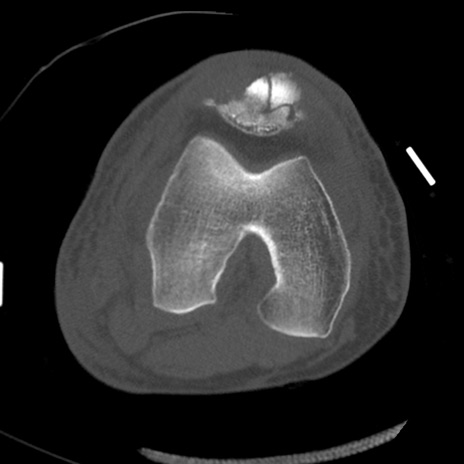

症例28 右膝関節CT(横断像)

右膝関節CT